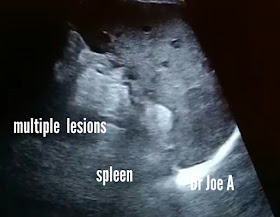

Multiple abscesses spleen, sonography

This spleen appears mildly enlarged with minute cystic areas.

Color Doppler ultrasound of the spleen shows increased vascularity.

Among the diagnostic possibilities:

Multiple abscesses

Miliary Kochs

Metastasis is also a remote possibility.